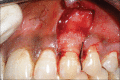

Aim: The aim of this study was to determine whether the addition of an autologous platelet rich fibrin (PRF) membrane to a coronally advanced flap (CAF) would improve the clinical outcome in terms of root coverage, in the treatment of isolated gingival recession.

Materials and methods: Systemically healthy 20 subjects each with single Miller's class I or II buccal recession defect were randomly assigned to control (CAF) or test (CAF + PRF) group. Clinical outcome was determined by measuring the following clinical parameters such as recession depth (RD), recession width (RW), probing depth (PD), clinical attachment level (CAL), width of keratinized tissue (WKT), gingival thickness (GTH), plaque index (PI), and gingival index (GI) at baseline, 3(rd), and 6(th) month postsurgery.

Results: The root coverage was 65.00 ± 44.47% in the control group and 74.16 ± 28.98% in the test group at 6(th) month, with no statistically significant difference between them. Similarly, CAL, PD, and WKT between the groups were not statistically significant. Conversely, there was statistically significant increase in GTH in the test group.

Conclusion: CAF is a predictable treatment for isolated Miller's class I and II recession defects. The addition of PRF to CAF provided no added advantage in terms of root coverage except for an increase in GTH.